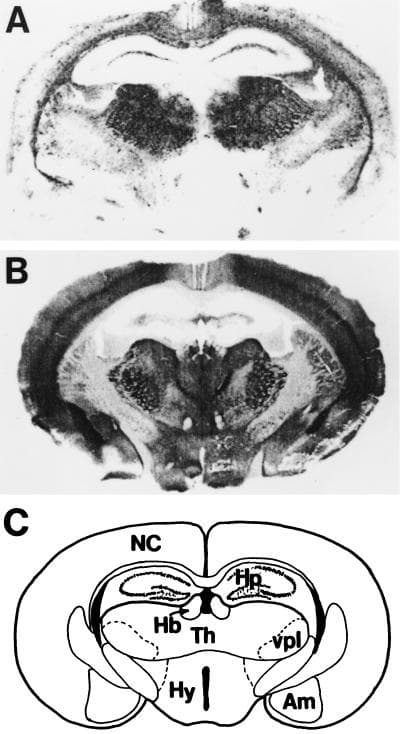

El cerebro de estos animales presentaba un aspecto de esponja, de donde proviene el término "espongiforme".

Los priones son los agentes causantes de patologías letales características de los mamíferos, conocidas como encefalopatías espongiformes transmisibles.

Ejemplos de estas enfermedades es la encefalopatía espongiforme bovina (EEB, conocida como la enfermedad de las “vacas locas”) en el ganado y la enfermedad de Creutzdeldt-Jakob (ECJ) en humanos.

Es probable que los priones no patógenos participen en procesos como la formación de la memoria a largo plazo, la memoria inmunitaria y la evolución del genoma de muchos organismos. Sin embargo, cuando se convierten en patógenos pueden convertir cerebros en esponjas.